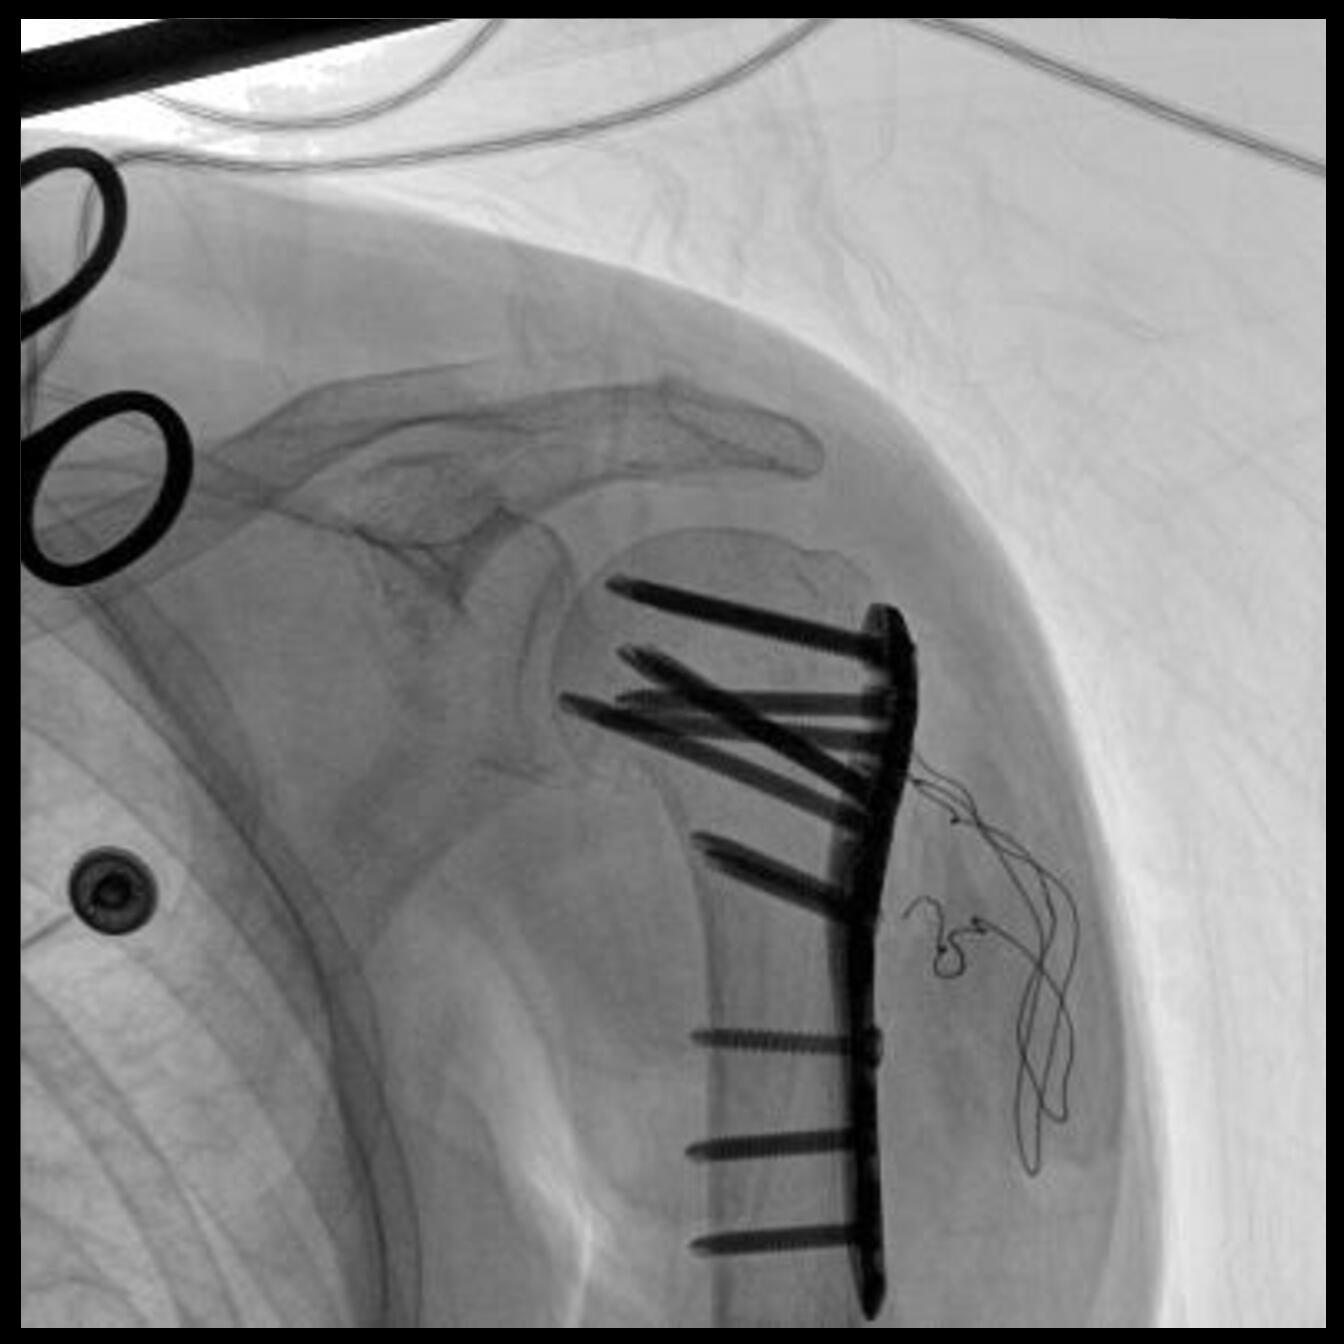

配備了兩種平板尺寸,大尺寸動態(tài)平板探測器成像面積較傳統(tǒng)平板探測器提升了25%以上,在視野需求大的手術中,便于醫(yī)生更好定位病灶點,規(guī)劃手術方案,減少因視野范圍不足而多次透視、點片造成的不便。

Clinical picture

臨床圖片